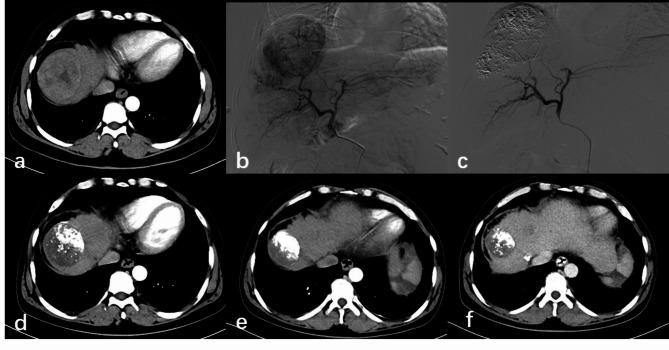

This study aimed to assess the effectiveness and safety of 5-Fluorouracil (5-Fu) combined with conventional transarterial chemoembolization (cTACE) compared to 5-Fu combined with drug-eluting bead transarterial chemoembolization (DEB-TACE) using CalliSpheres for the treatment of unresectable hepatocellular carcinoma (HCC) using propensity score weighting methods. This retrospective analysis included 131 patients with HCC treated with 5-Fu combined with cTACE (5-Fu-cTACE group, n = 65) or DEB-TACE (5-Fu-DEB-TACE group, n = 66) at the Affiliated Hospital of North Sichuan Medical College from January 2019 to December 2022. Based on the baseline data and laboratory indicators, propensity score weighting was used to reduce confounding bias. Modified response evaluation criteria in solid tumors (mRECIST) were used to evaluate clinical efficacy. The primary endpoint was progression-free survival (PFS), and the secondary endpoints were the disease control rate (DCR), objective response rate (ORR) and adverse events (AEs). PFS was assessed using Kaplan‒Meier analysis and Cox proportional hazards models. The ORRs at 1 month (M1) after treatment in the 5-Fu-DEB-TACE group and 5-Fu-cTACE group were 90.9% and 76.9%, respectively (P = 0.029), while at this time, the DCRs were 93.9% in the 5-Fu-DEB-TACE group and 90.8% in the 5-Fu-cTACE group (P = 0.494). At 3 months (M3) after treatment, the 5-Fu-DEB-TACE group had a higher ORR (84.8% vs. 56.9%, P < 0.001) and DCR (84.8% vs. 72.3%, P = 0.08). The ORR at 6 months (M6) was also higher in the 5-Fu-DEB-TACE group than in the 5-Fu-cTACE group (72.7% vs. 50.8%, P = 0.01). The median PFS after treatment with 5-Fu-DEB-TACE was longer than that after treatment with 5-Fu-cTACE (11 months vs. 6 months) (P = 0.004). Cox proportional hazards regression analysis indicated that 5-Fu-DEB-TACE (HR = 0.590, P = 0.044), Model for End-Stage Liver Disease (MELD) intermediate risk (HR = 2.470, P = 0.010), BCLC stage B (HR = 2.303, P = 0.036), BCLC stage C (HR = 3.354, P = 0.002) and ascitic fluid (HR = 2.004, P = 0.046) were independent predictors of PFS. No treatment-related deaths occurred in this study. The 5-Fu-DEB-TACE group had a greater incidence of abdominal pain (72.7% vs. 47.7%, P = 0.003). However, the incidence of postoperative elevated transaminase levels was higher in the 5-Fu-cTACE group (83.1% vs. 66.6%, P = 0.031). Subgroups analysis showed patients receiving 5-Fu-DEB-TACE have better PFS compared to those receiving 5-Fu-cTACE in the BCLC stage A group (P = 0.0093), BCLC stage B group (P = 0.0096), multifocal group (P = 0.0056), Child-Pugh stage A group (P<0.001), non- extrahepatic metastasis group (P = 0.022), non-vascular invasion group (P = 0.0093), and the group with a largest tumor diameter ≥ 5 cm (P = 0.0048). At M1, M3, and M6, patients with preserved liver function and in some cases of low tumor burden had higher Objective Response Rate (ORR) and Disease Control Rate (DCR) (P < 0.05). Compared with 5-Fu-cTACE, 5-Fu-DEB-TACE has superior therapeutic efficacy, prolongs PFS, and reduces hepatotoxicity. However, it is associated with an increased incidence of postoperative abdominal pain.